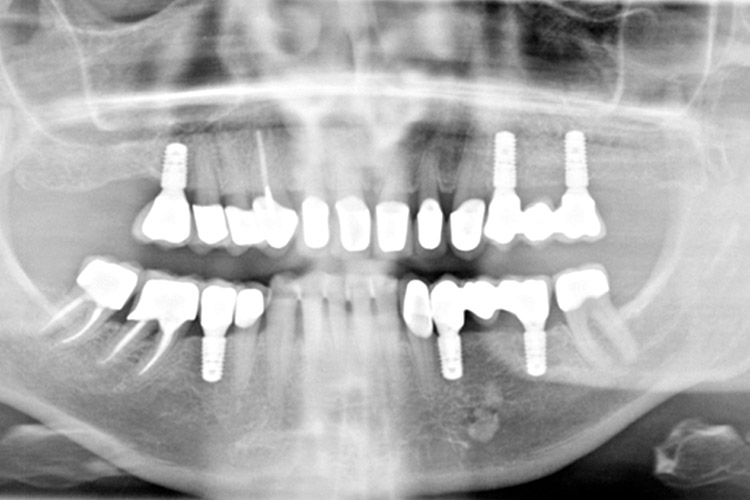

Röntgenbild von Implantaten und festsitzendem ZahnersatzDie Therapie mit Implantaten ist ein in der Zahnmedizin ein nicht mehr weg zu denkender Fortschritt. Seit über 60 Jahren ist „Osseointegration“, der Verbund von Knochen mit Zahnimplantaten aus Titan, bekannt und wissenschaftlich beschrieben. Implantate können in allen Regionen des Ober- und Unterkiefers eingesetzt werden. Dabei besteht die Möglichkeit einzelne Zähne, festsitzende Brücken oder auch herausnehmbaren Zahnersatz auf Implantaten abzustützen. Entscheidend für den Erfolg ist dabei maßgeblich das Behandlungskonzept. Durch wissenschaftliche Fachgesellschaften, z.B. das ITI (International Team for Implantology)